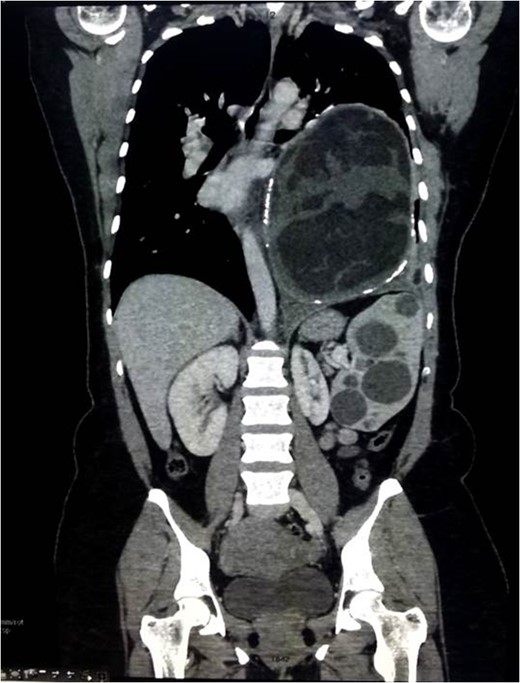

Chest x-ray showed well-defined huge opacity of most left hemithorax with a shift of mediastinum to the right (Fig. 1). CT chest/abdomen/pelvis with IV contrast revealed 20 × 15 × 18 cm3 well-defined mixed cystic lesion within the left lung containing multiple parts of the heterogeneous density with soft tissue elements and fat content. It also showed spots of wall calcification, where the lesion probably originated from the mediastinum, involving most of the left hemithorax. The mass compressed the mediastinal structures, great vessels, and airways (Fig. 2). It is surrounded by a consolidation collapsed with a marked shift of mediastinum to the right side (Figs 2 and 3). No mediastinal lymphadenopathy and the right lung was clear. The spleen was enlarged with multiple cysts that varied in size with no significant enhancement post IV contrast in arterial and portal phases (Figs 2 and 4). The liver was unremarkable. Hematological tests were within normal limits. Mantoux test and Sputum culture were negative.